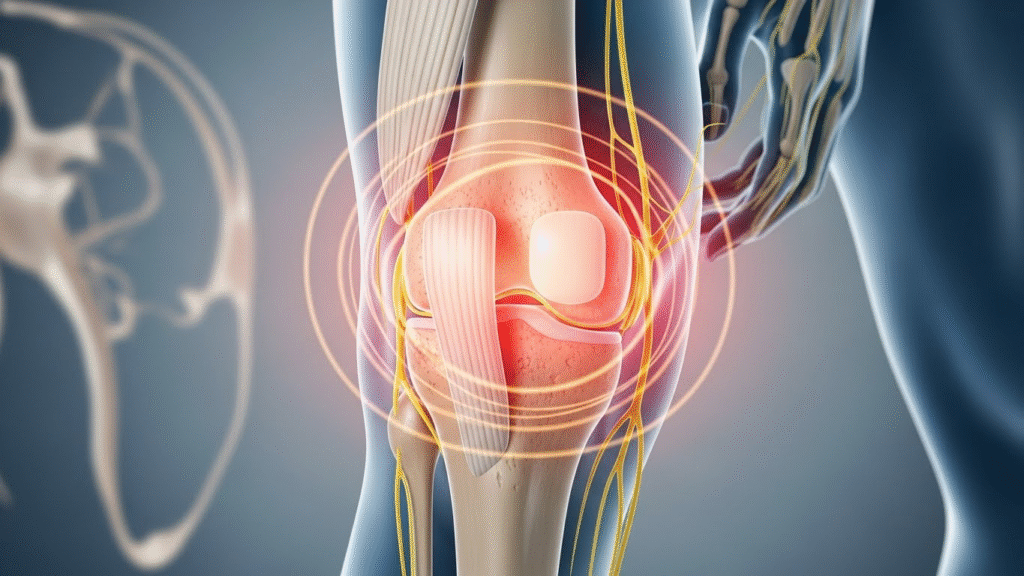

A healthy joint includes bones cartilage synovial fluid ligaments tendons and muscles. Cartilage is a smooth cushion that covers the ends of bones. It allows bones to glide over each other without pain. Synovial fluid acts like oil in a machine reducing friction and nourishing the joint.

Attrities begins when one or more of these parts become damaged inflamed or worn down.

In attrities the balance inside the joint is disturbed. Depending on the type of attrities different problems can occur.

Cartilage may wear away causing bones to rub together. The immune system may attack the joint lining causing swelling and pain. Crystals may form inside the joint causing sudden sharp pain. Old injuries may lead to long term damage.

The body responds with inflammation. Inflammation is the immune system’s way of trying to heal but when it becomes long term it causes more harm than good.

This ongoing inflammation leads to pain stiffness swelling warmth redness and loss of movement.